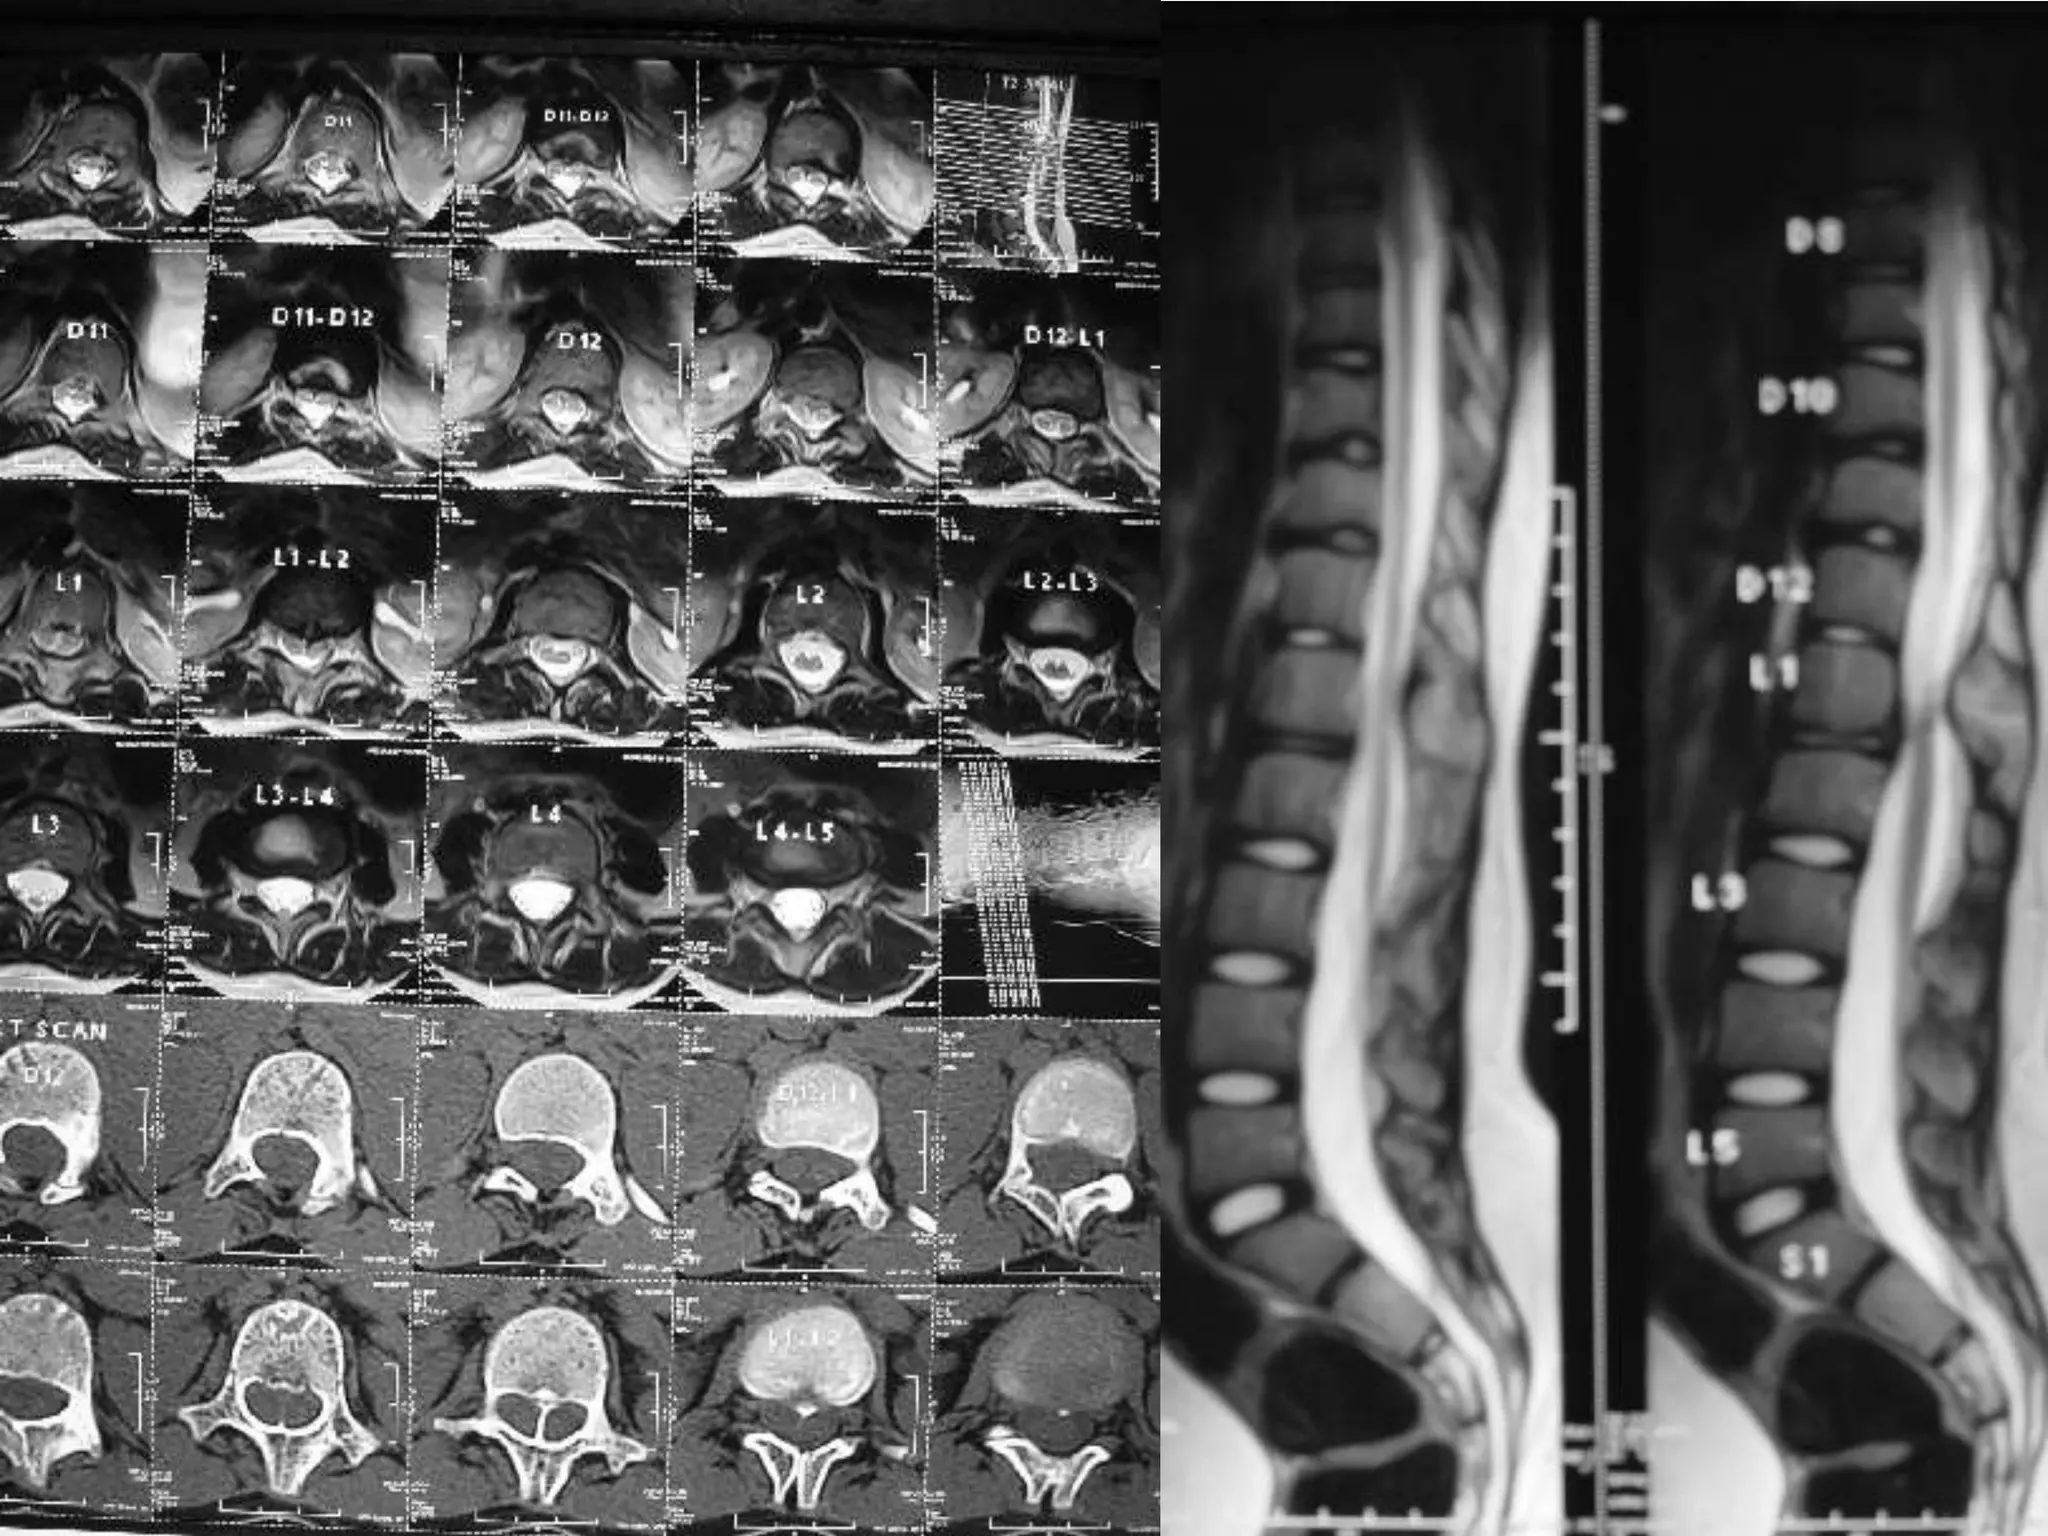

Dorsal Discs

Disc at D12 – L1

Post operative Right sided Facetactomy